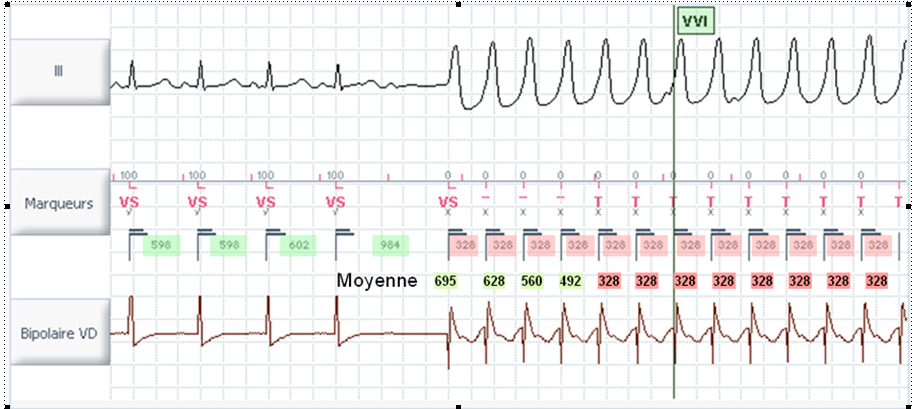

La classification des intervalles est basée sur la durée RR instantanée et la moyenne des 4 derniers cycles.

Le DAI mesure les intervalles et les compte dans des cases. Un intervalle est la période de temps (en millisecondes) entre un intervalle et le suivant (rythmé et/ou détecté) dans une chambre. L'intervalle actuel (CI) est l'intervalle de temps entre les événements ventriculaires détectés. L'intervalle moyen (AI) est la moyenne des quatre intervalles les plus récents.

Pour classer un intervalle, le DAI doit savoir comment le classer (FV, VT-1, VT-2, NSR [rythme sinusal normal]). Si l'intervalle moyen = l'intervalle actuel, l'intervalle est classé dans cette zone. Si l'intervalle moyen ou l'intervalle actuel est classé comme NSR, l'intervalle est éliminé. Si l'intervalle moyen et l'intervalle actuel sont différents (mais pas NSR), l'intervalle est classé dans la zone la plus élevée.

Les intervalles sont comptés jusqu'à ce qu'un bac atteigne sa capacité. Lorsqu'un emplacement est plein, ce rythme particulier est “détecté”.

Tous les compteurs fonctionnent simultanément :

- Compteur VT lent (VT-1)

- Compteur VT rapide (VT-2)

- Compteur VF (VF)

- Retour au compteur de rythme sinusal

Une incrémentation du compteur de la zone la plus rapide n'incrémente pas le compteur des zones plus lentes.

Le premier compteur atteignant le nombre de cycles programmés détermine la détection, le type d'événement et, éventuellement, la (les) thérapie(s) délivrée(s). Ces cycles ne sont pas nécessairement consécutifs. Il en va de même pour la redétection post-thérapeutique, qui dispose de ses propres compteurs, distincts.

Dans cet exemple, l'appareil est configuré en trois zones, toutes les cases étant réglées sur 12 intervalles. Le 12e T est encerclé ; c'est le point où la TV est diagnostiquée.